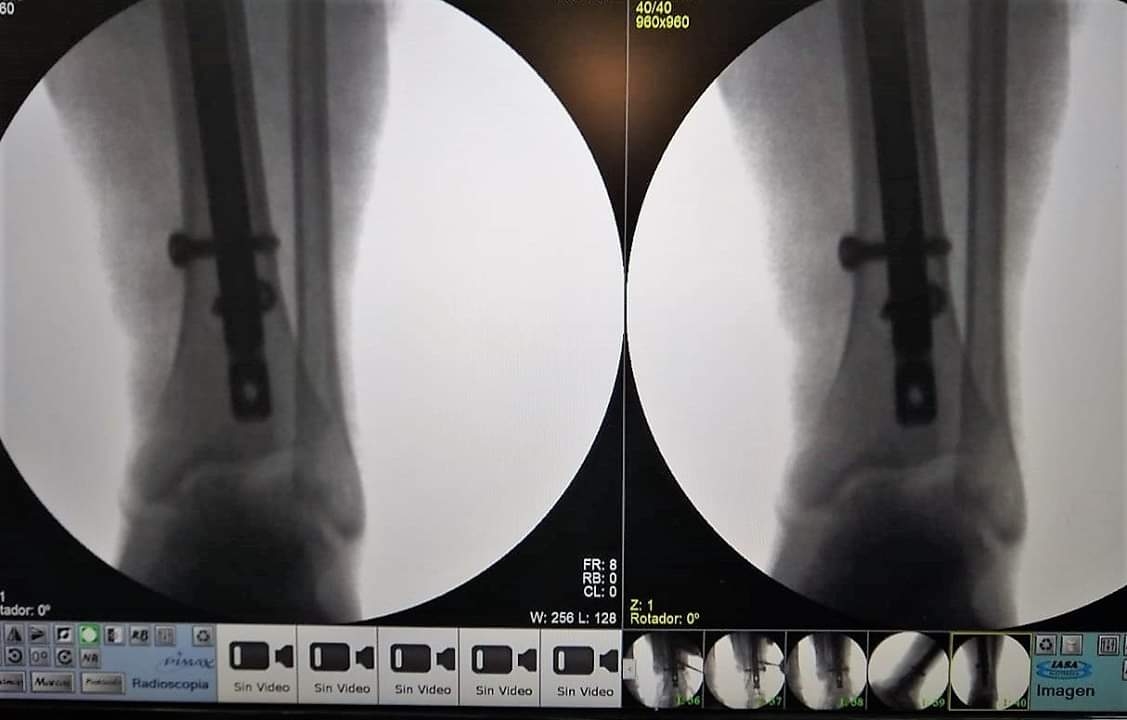

Esta intervención quirúrgica requirió la colocación de un clavo endomedular acerrojado de titanio en tibia.

Si bien se hacían muchos tipos de intervenciones quirúrgicas históricamente, este tipo de operaciones son posibles desde que el Hospital de Recreo cuenta con un Arco en C, aparato especializado en imágenes de Rayos X que permitió un salto de calidad en cirugías traumatológicas de mayor complejidad.

Hasta hace poco más de un año, las cirugías traumatológicas en Recreo eran más sencillas; las fracturas complejas debían ser derivadas a otros centros porque no se podía operar. Sin el Arco en C es imposible realizar estos procedimientos, porque el cirujano necesita tener una imagen en vivo para poder evaluar si el material está correctamente colocado.